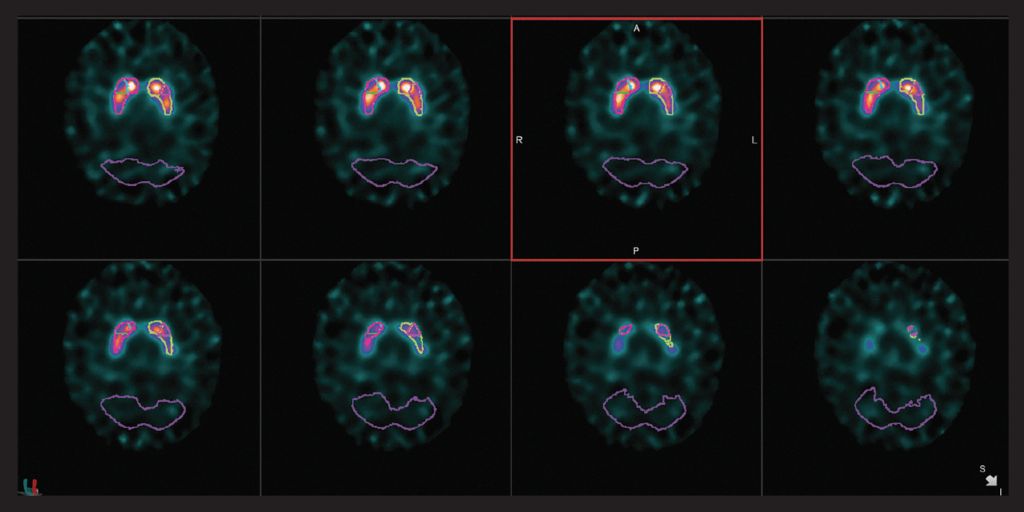

心臟

VERITON ? 采用我們成熟的CZT探測器技術(shù),可實(shí)現(xiàn)更好的協(xié)議優(yōu)化??紤]使用如此處所示的標(biāo)準(zhǔn)劑量的高分辨率2分鐘MPI采集,或選擇顯著更低的劑量同時保持短的采集時間。通過擴(kuò)展示蹤劑使用來檢查增加未來心臟實(shí)踐的方法。